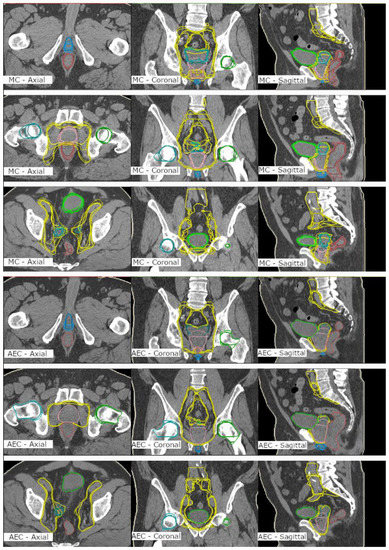

1. Introduction

2. Materials and Methods

2.3. Contouring

- An MC group contoured in the study into an empty dataset to meet clinical acceptance.

- An AC group that included the nonedited automatically created structure set.

- An AEC group that included the automatically created structures with expert modifications to meet clinical acceptance.